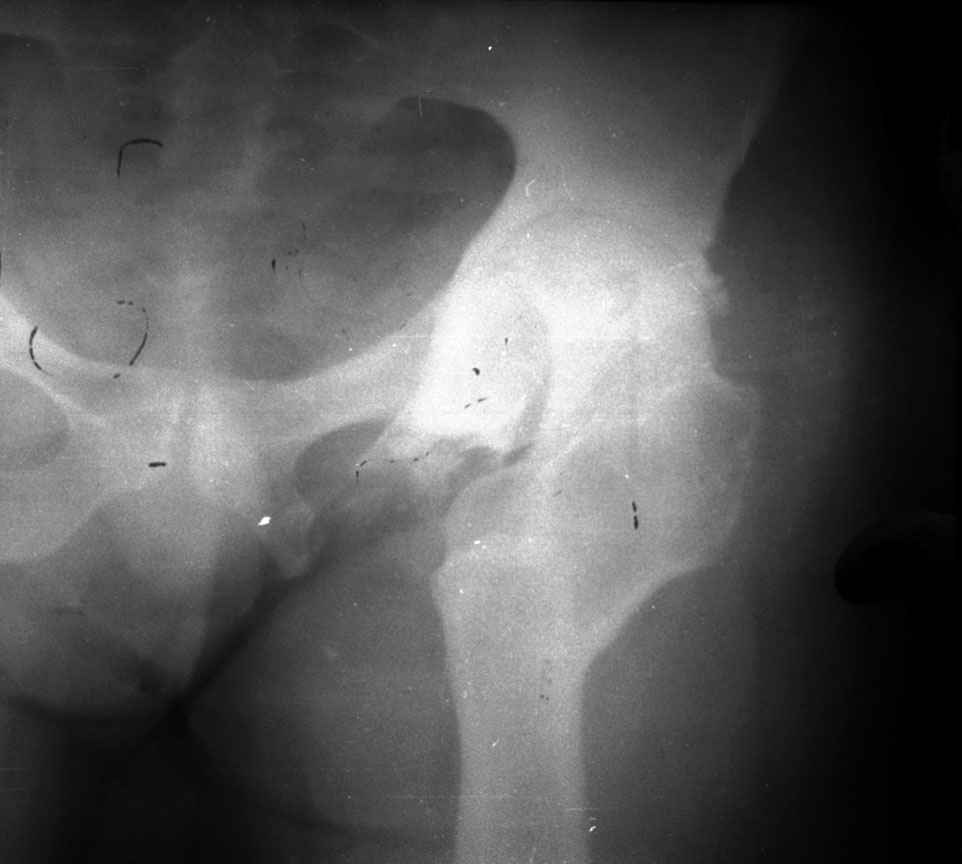

остеотомии. Я представил Р-граммы больных с неудачными р-ми после остеотомий.

Эндопротезирование у них было на порядок сложнее в отличие от артропластики без проведения остеотомии.

.........наверное не повезло. Но иногда это выход и очень хороший. М., 21 года спрыгнул в Армии с машины с исходом в гнойный коксит, свищевой формой в течении 1,5 лет. Операция проведена в 1988 году. результат хороший и сейчас и мы с пациентом хорошие приятели (Рентг-гр и фото прилагаю).